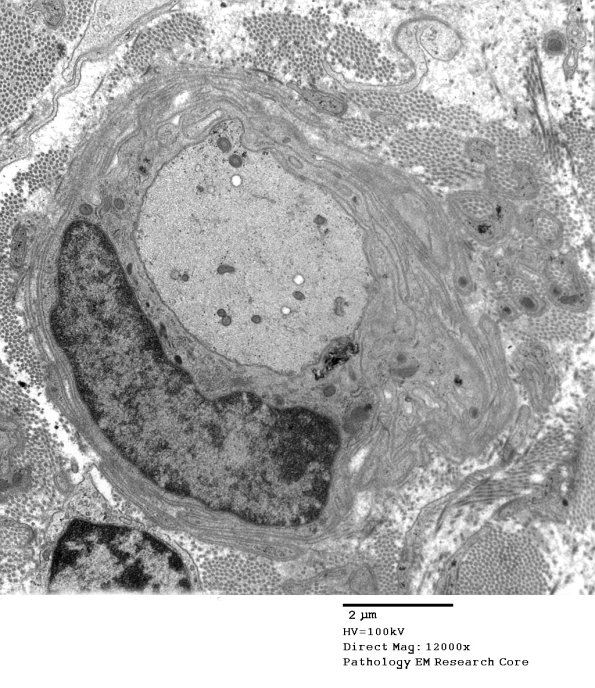

Multiple examples of demyelinated large axons, many surrounded by numerous delicate macrophage processes. (electron micrographs)